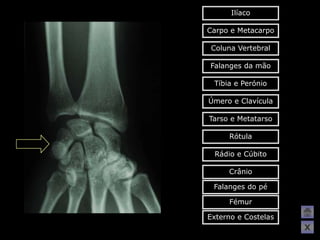

O   Aqui tens de conseguir acertar na

resposta, só assim poderás avançar

para a figura seguinte!!!

Ilíaco Carpo e Metacarpo Coluna Vertebral Falanges da mão Tíbia e Perónio Úmero e Clavícula Tarso e Metatarso Rótula Rádio e Cúbito Crânio Falanges do pé Fémur Externo e Costelas X